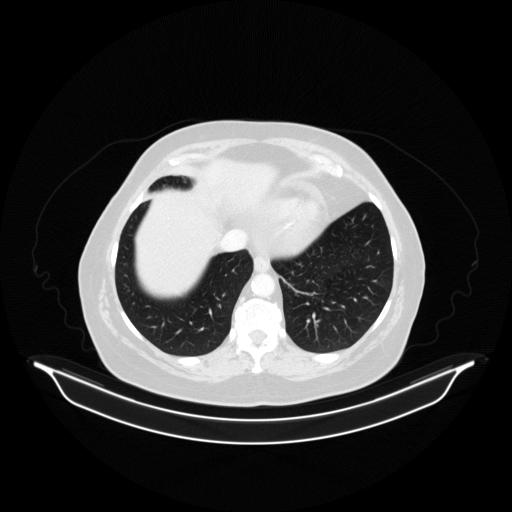

Image Grid

4Γ—3 grid: Rows show different image types (Original NATIVE, Reconstructed NATIVE, Original VENOUS, Generated VENOUS), Columns show windowing techniques (No Window, Lung Window, Mediastinum Window)

Generated VENOUS CT scan (A→B translation)

Lung window (WL -600, WW 1500 β†’ Low βˆ’1350, High +150)